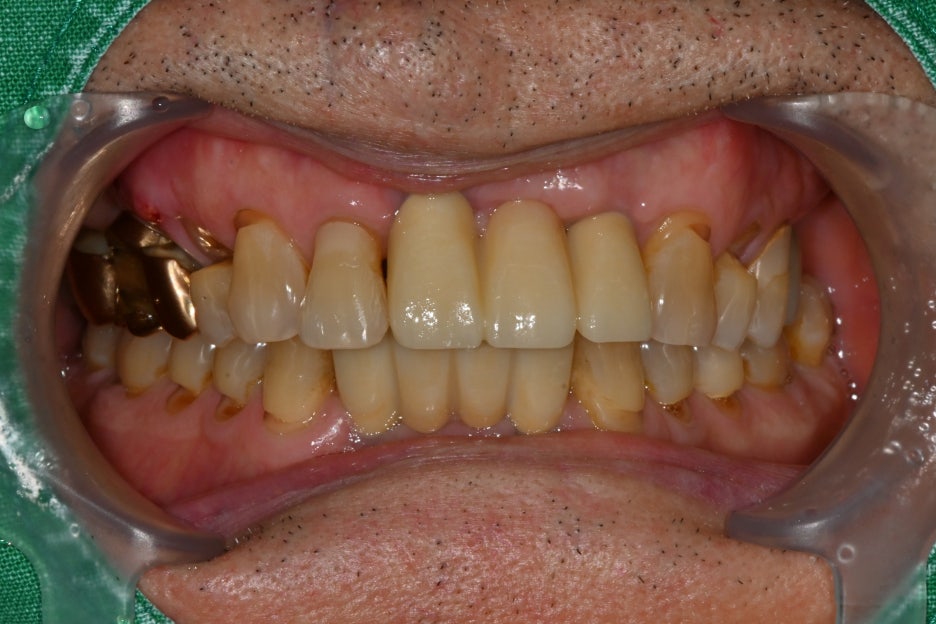

⑤ 보철물 제작 및 장착

– 원내 기공소에서 지르코니아 크라운을

맞춤 제작했습니다.

– 앞니는 자연스럽고 밝은 톤, 어금니는 강도와 내구성을

고려하여 제작했습니다.

치료결과

치료를 마친 환자분은

앞니가 다시 복원되어 웃을 때

자신감이 생겼고, 음식도 편하게

씹을 수 있게 되었어요.

크게 만족하셨습니다.

또한 얼굴 상처도 흉터가 최소화되어

주변에서 사고 흔적을 거의 알아보지 못했다고 하셨습니다.